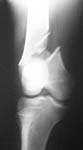

Hip and knee normal. Will post the pictures at the earliest.

Images of knee and hips.